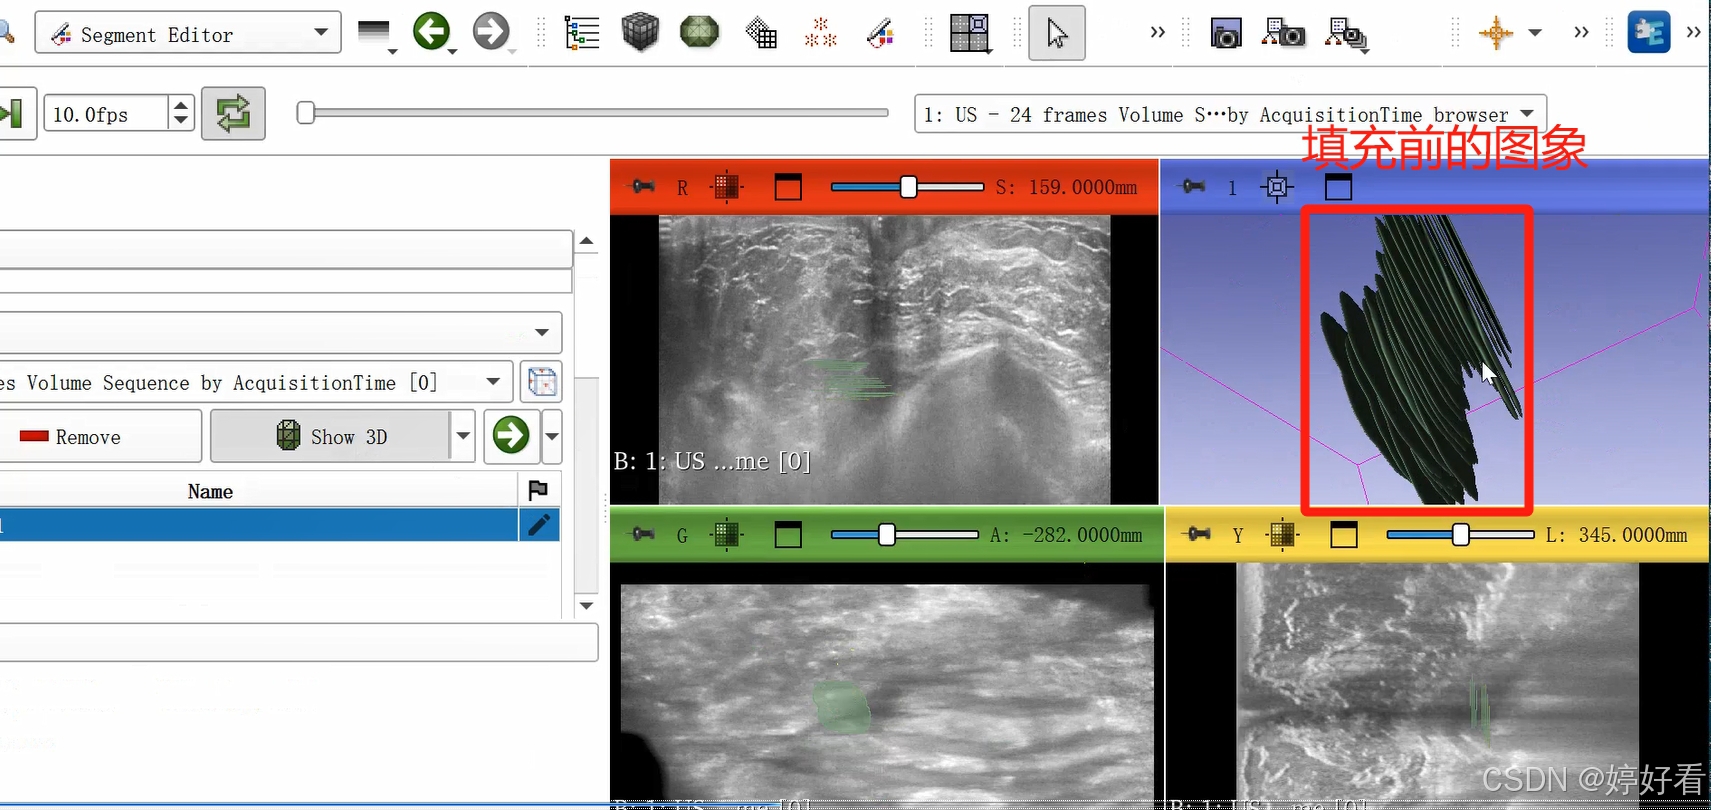

上一步中完成的三维图像不是完整连续的三维图像,是一层一层的。Fill between slices这个功能可以自动填充每一层之间的间隙。选中Fill between slices,然后依次点击Initialize-Apply。